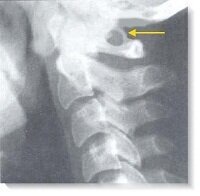

Итак, аномалия Киммерли - это лишнее костное образования в области задней дуги первого шейного позвонка над позвоночной артерией. Такой костный "мостик" может быть с одной или с обеих сторон, а также полным или неполным.

Пример того, как аномалия (синдром) Киммерли выглядит на рентгеновском снимке